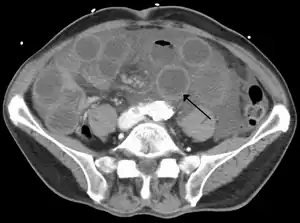

Computed tomography (CT) showing dilated loops of small bowel with thickened walls (black arrow), findings characteristic of ischemic bowel due to thrombosis of the superior mesenteric vein.

Computed tomography (CT scan) is often used.[29][30] The accuracy depends on whether a small bowel obstruction (SBO) is present.[31]

Early findings include:

• Mesenteric edema[29]

• Bowel dilatation[29]

• Bowel wall thickening[29]

• Mesenteric stranding[32]